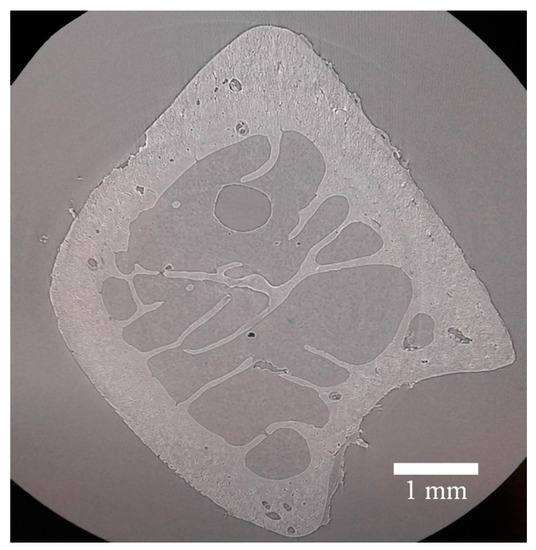

3.1. Tomography, Reconstruction and Segmentation